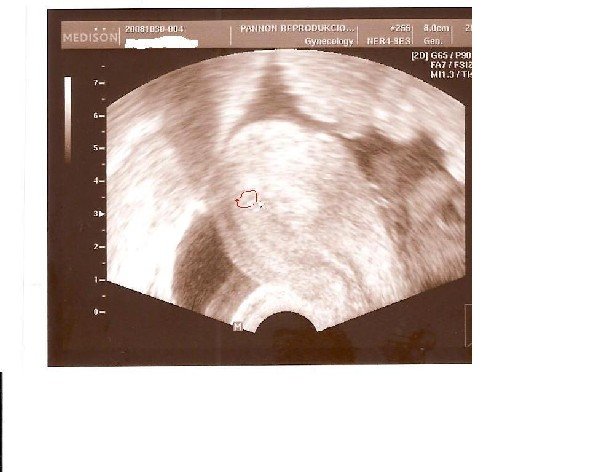

UH-n mi volt? Képek????